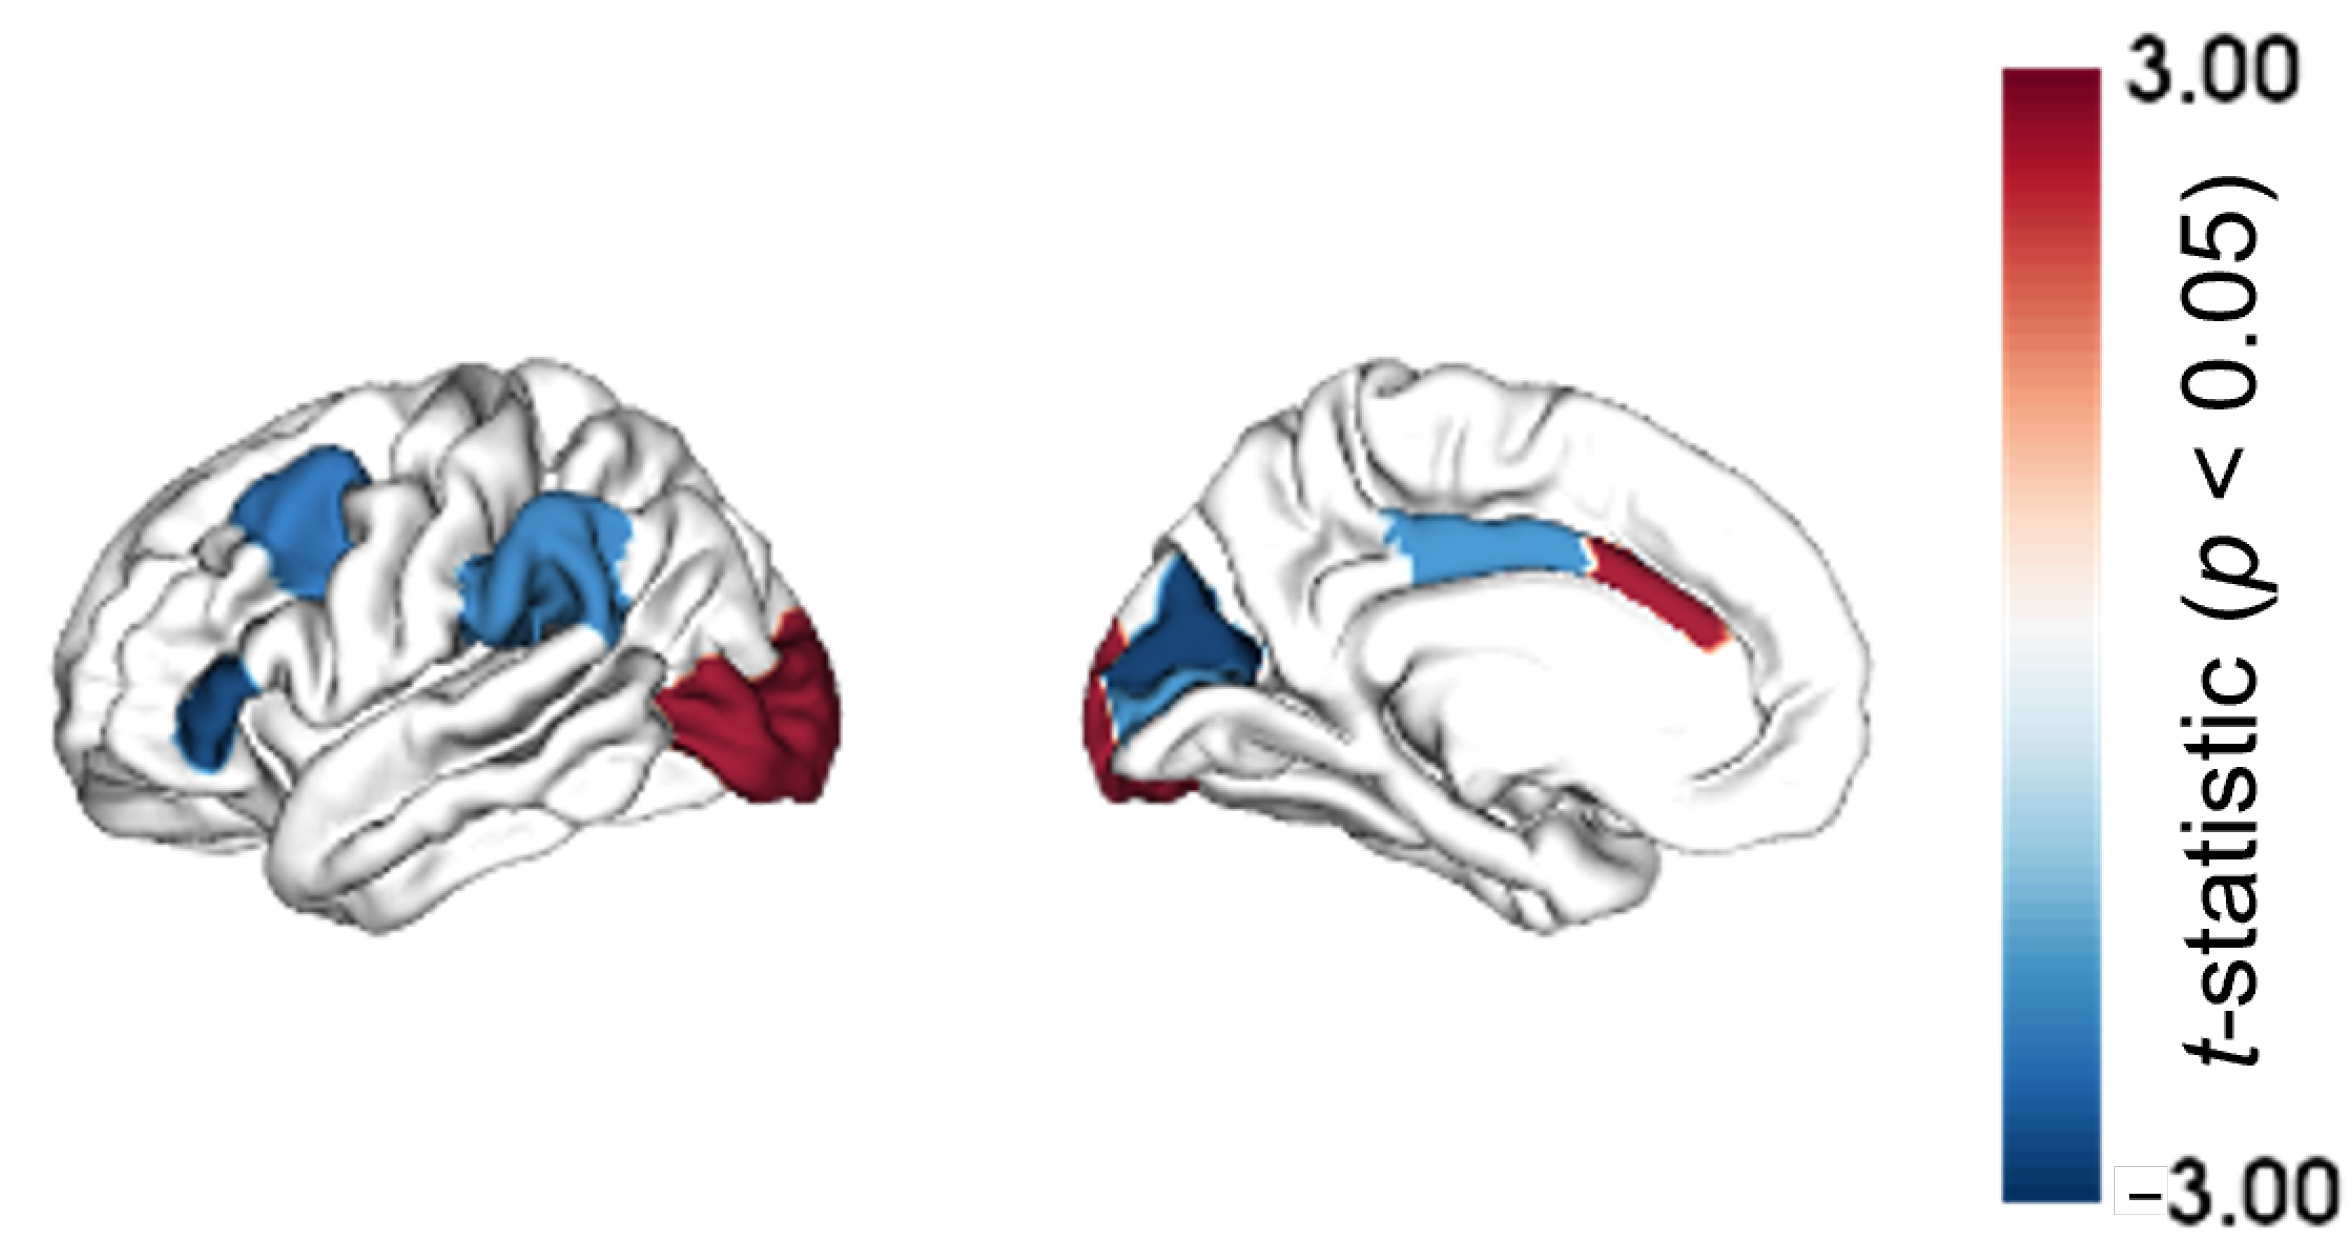

2.1. Regional Morphometric Similarity Group-Wise Differences